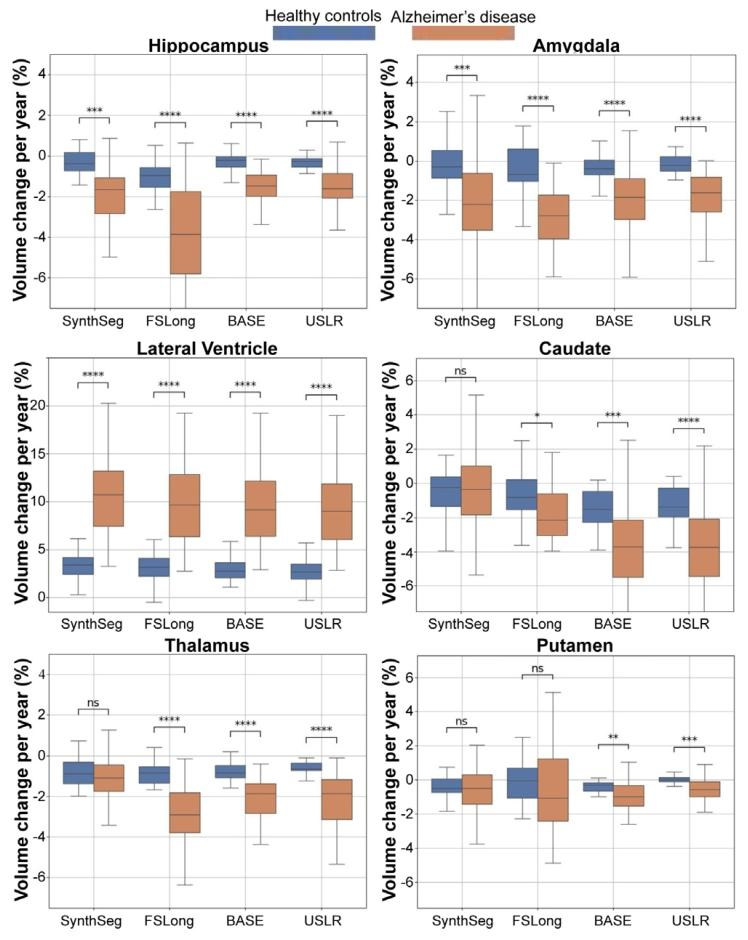

Fig. 9. Sensitivity analysis computing the trajectory’s slope of 6 different ROI volumesper subject. In each figure, we compare three different segmentation methods. From leftto right: cross-sectional SynthSeg, the longitudinal stream of Freesurfer, a longitudinalrefinement using the baseline image as template and our USLR framework. Cognitivelynormal subjects are grouped in blue while AD subjects in dark orange. Significantdifferences in mean slopes are found in a Wilcoxon-rank test between groups for (*)1 ⋅ 10−2 < 𝑝 < 5 ⋅ 10−2 , () 1 ⋅ 10−3 < 𝑝 < 1 ⋅ 10−2 , (*) 1 ⋅ 10−4 < 𝑝 < 1 ⋅ 10−3 and ()𝑝 <* 1 ⋅ 10−4 thresholds.

图9 敏感性分析:计算每位受试者6个不同感兴趣区(ROI)体积的轨迹斜率。每张图中比较了三种不同的分割方法,从左到右依次为:横断面SynthSeg、FreeSurfer纵向流程、以基线图像为模板的纵向优化,以及我们的USLR框架。认知正常受试者以蓝色分组,阿尔茨海默病(AD)受试者以深橙色分组。通过Wilcoxon秩检验发现,组间平均斜率存在显著差异,显著性水平标注如下:()1×10⁻²<𝑝<5×10⁻²,(**)1×10⁻³<𝑝<1×10⁻²,(**)1×10⁻⁴<𝑝<1×10⁻³,()𝑝<1×10⁻⁴。